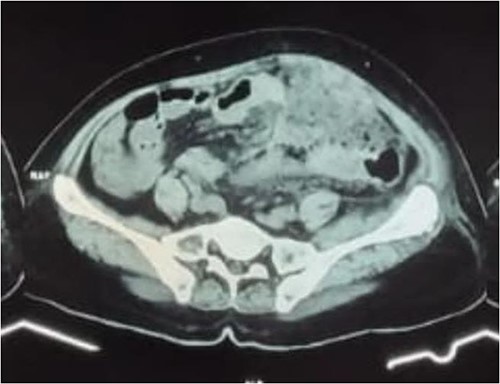

A 58-year-old female came to our emergency department with left-lower quadrant abdominal pain since 5 days before admission without nausea and vomiting. Three weeks before admission, she had history of urinary retention and constipation without history of fever. On physical examination, abdominal tenderness associated with a palpable mass was found on the left lower quadrant. The mass was ~15 cm in diameter. Her laboratory result showed increased level of white blood cells. We later performed abdominal X-ray, ultrasound (USG), and computed tomography scan (CT scan). The X-ray showed local obstruction in the right lower abdomen and USG revealed a left abdominal colon mass. For further evaluation, we conducted abdominal CT scan with contrast that showed thickening of the transverse, descending to sigmoid colon wall and intense contrast enhancement resembling colitis with mesenteritis (Fig. 1).

Abdominal CT scan with contrast showed transverse, descending to sigmoid colon wall thickening and significant contrast enhancement supporting colitis with mesenteritis.